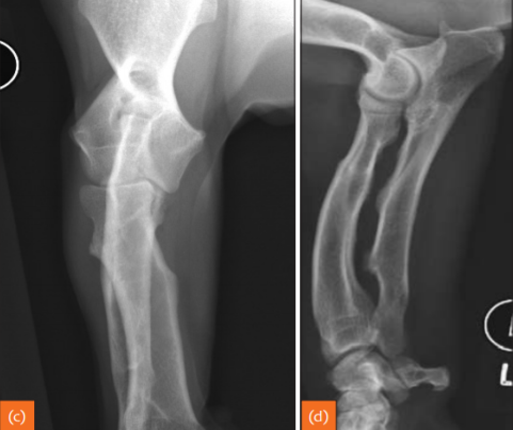

15

whats this

Chondrodystrophic breed changes. Not pathological, just a certain breed thing.

The long bones are affected but the joints themselves are not affected.